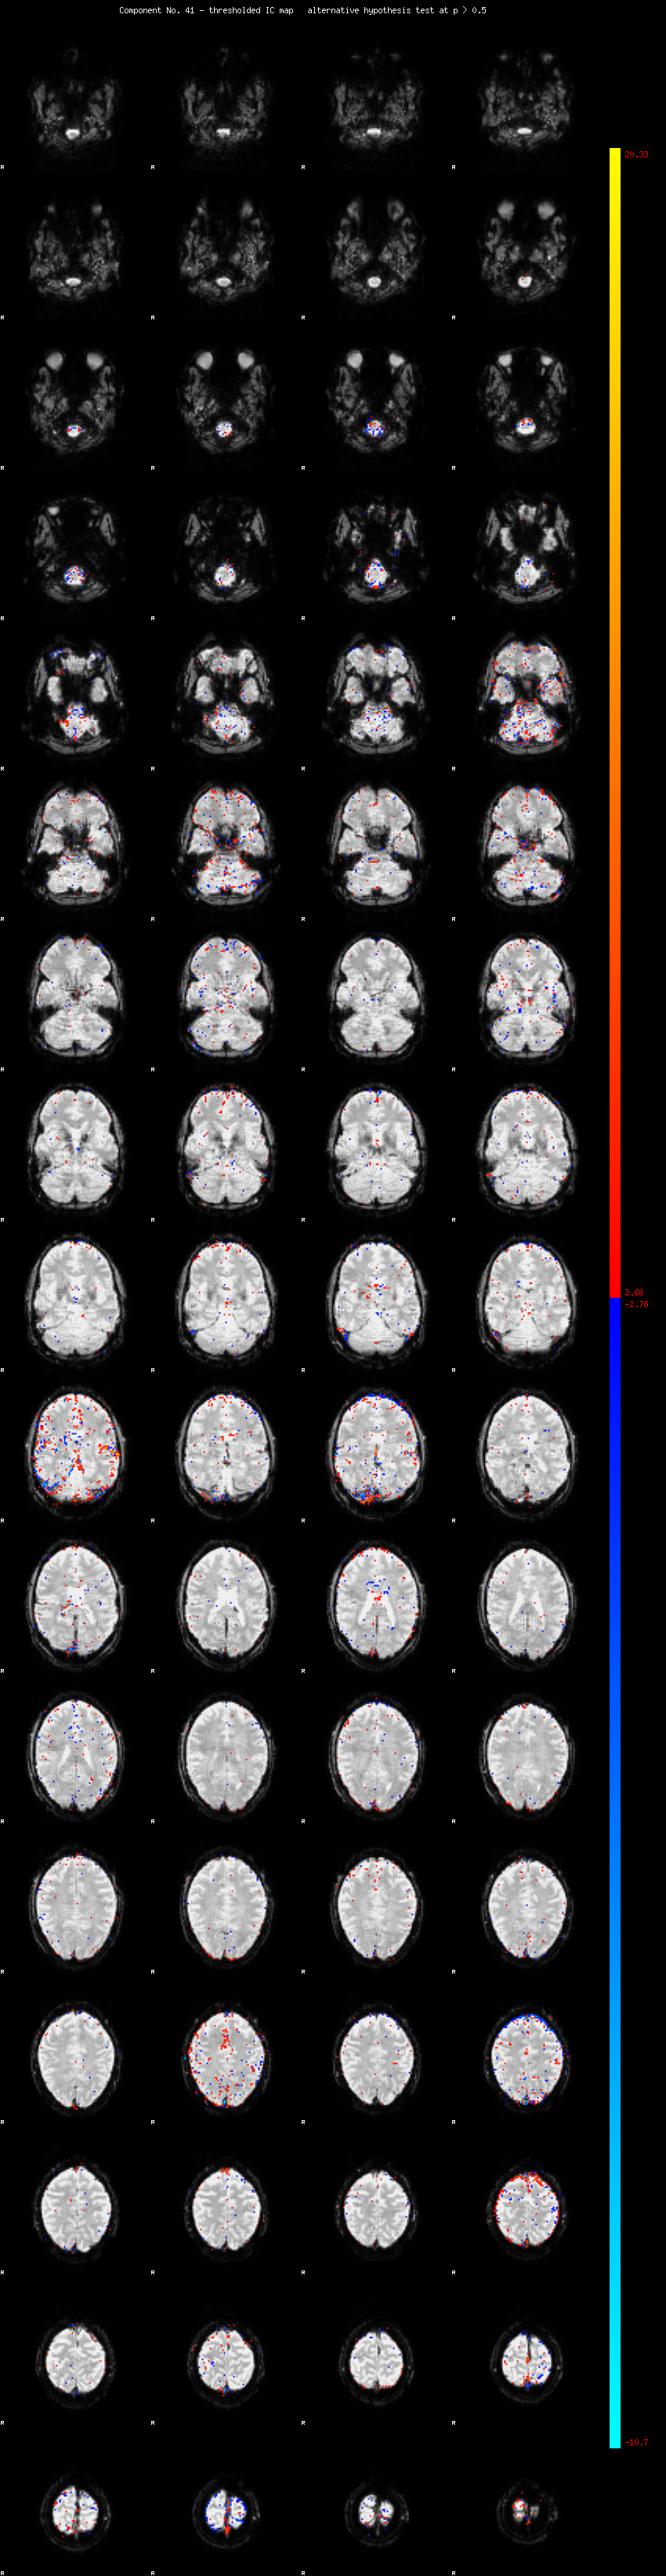

MELODIC Component 41

1.09 % of explained variance;     0.72 % of total variance